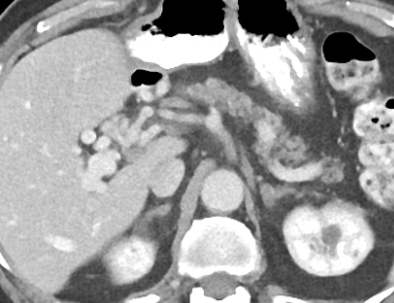

- Sur thrombose porte chronique ++

- Voie de dérivation Porto-Porte (contrairement à porto-systémique du reste de l’hypertension portale)

- Péri-veine porte et Lit vésiculaire ++

- Le Cavernome se développera surtout sur un foie sain avec occlusion porte rapide